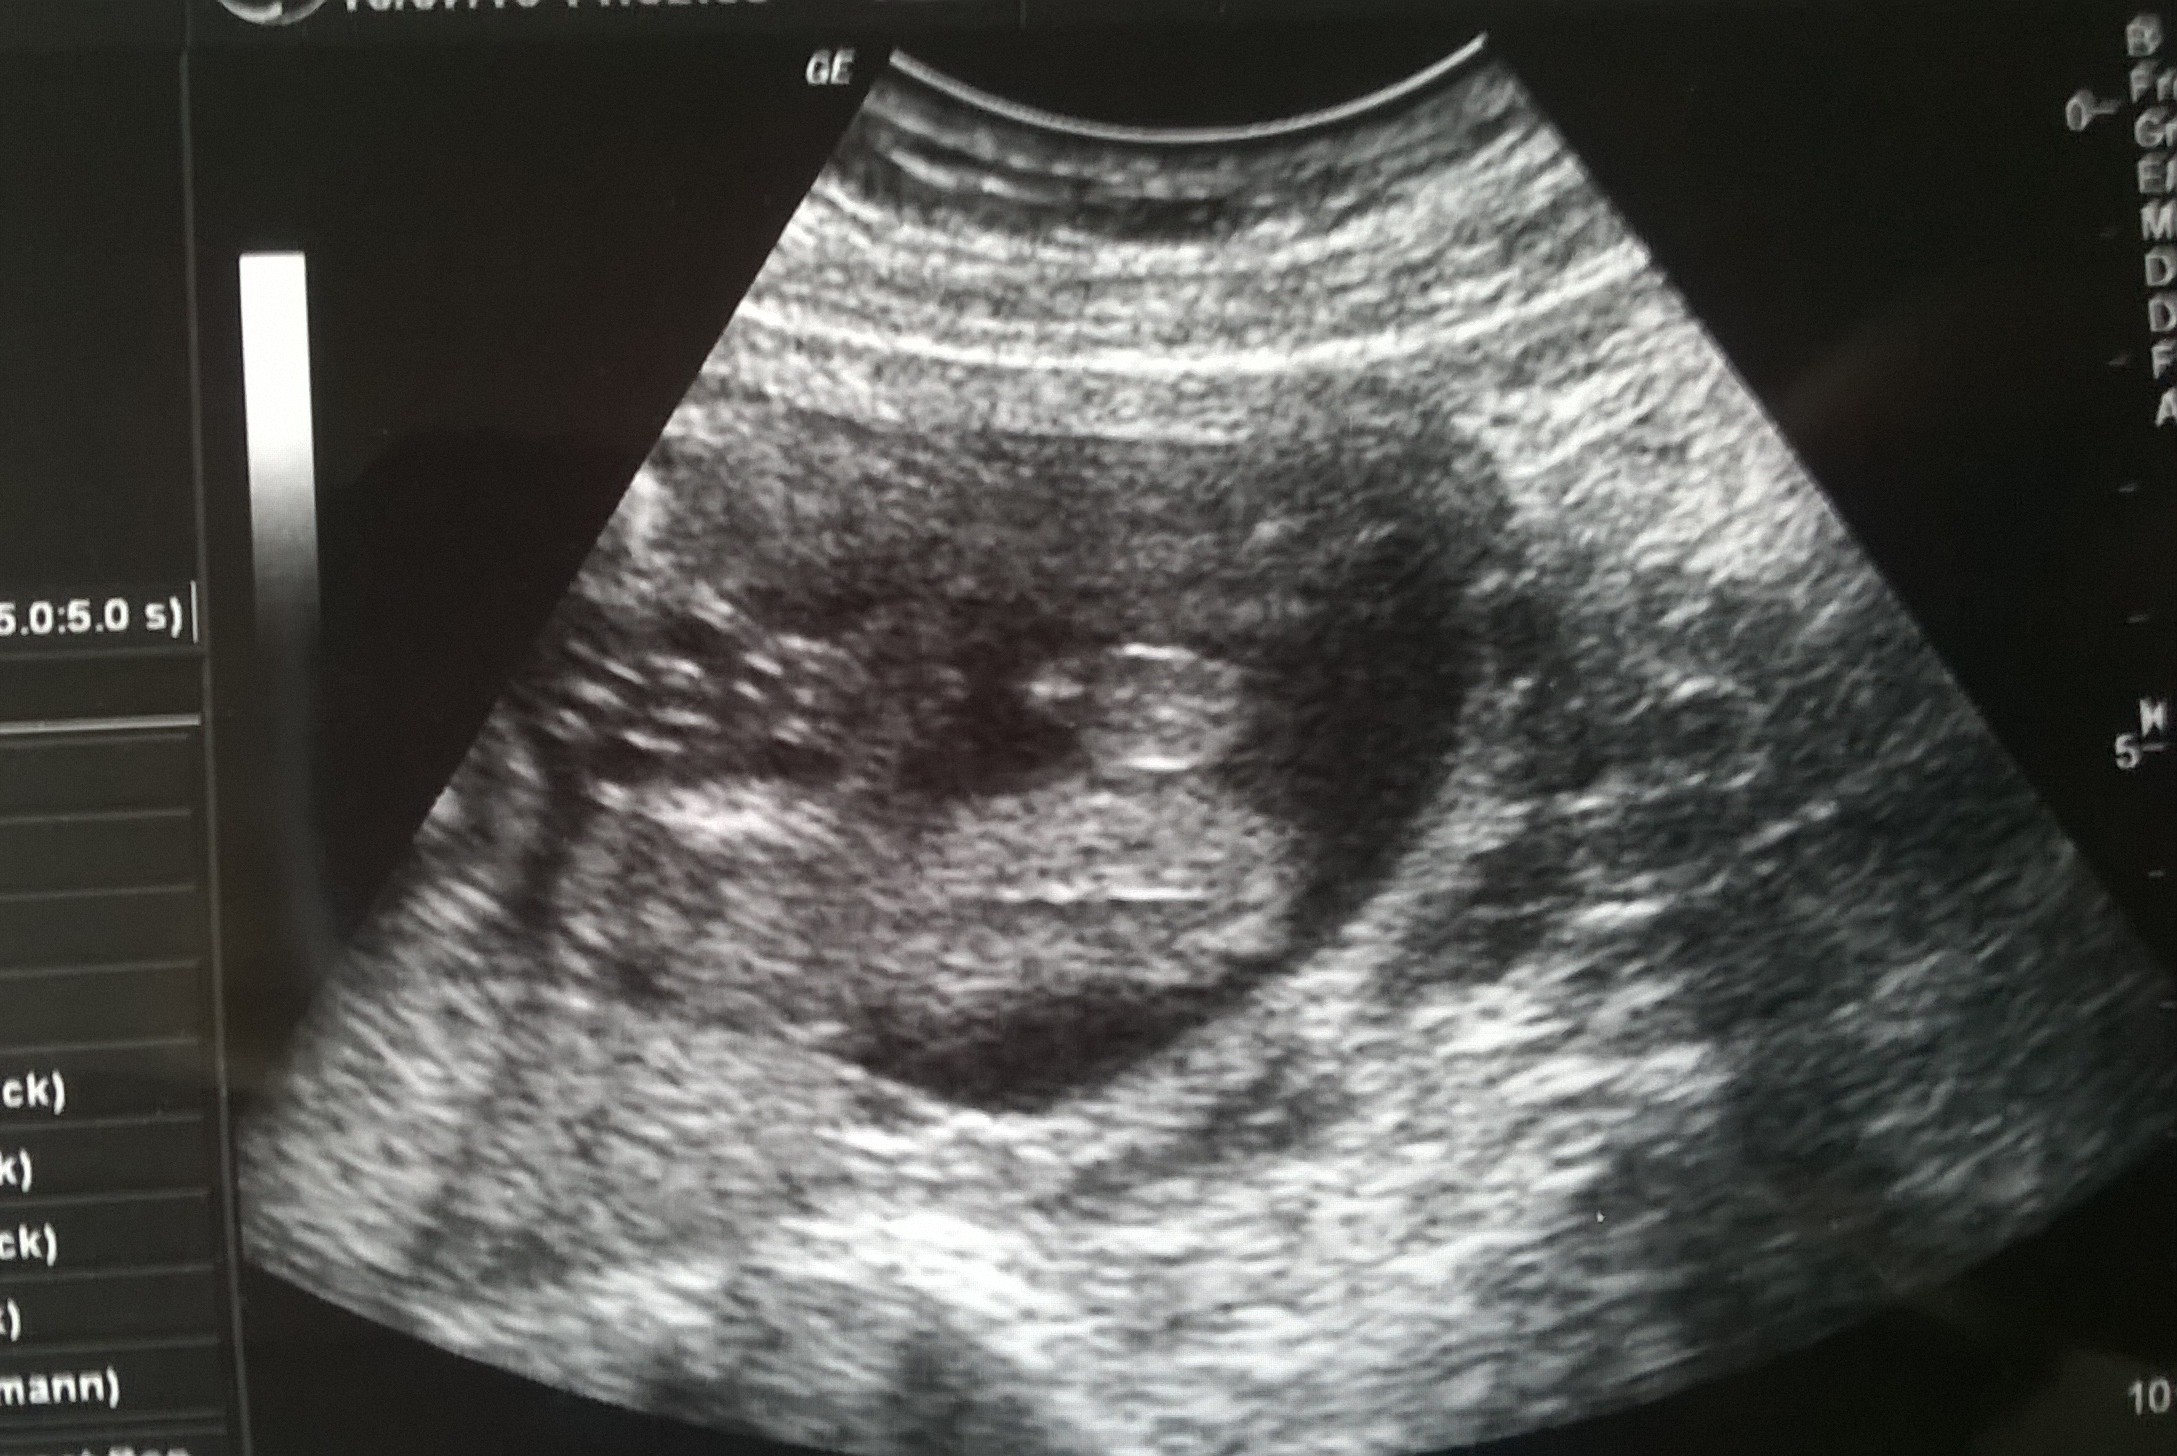

GratulacjePo USG polowkowym.

Wsxystko ladnie doktoreczka pomierzyla

Wnioski:Anatomia prawidlowa

Lozysko sciana tylna

Stopien dojrzalosci 0

Ilosc plynu owodniowego prawudlowa

Szyjka 3.95

FHR 146/min

Tydzien ciazy 21.2

Waga 467g ❤♥♥♥

Moj synio ♥♥♥